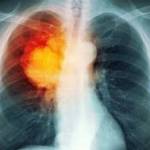

Инструментальная диагностика играет ключевую роль в выявлении центрального рака легкого. Из инструментальных методов исследования привлекаются:

- флюорография – так называют рентгенографию органов грудной клетки в миниатюре. С ее помощью обследуют большое количество людей, чтобы не «пропустить» рак легких, при наличии признаков патологии направляют на рентгенографию грудной клетки;

- рентгенография органов грудной клетки – на рентгенологических снимках обнаруживают круглую тень в корне легкого, изменение легочного рисунка в соседних областях;

- компьютерные методы – компьютерные срезы позволяют изучить более подробно структуру легких, выявить опухоль и изучить ее строение. Привлекаются компьютерная томография (КТ) и ее усовершенствованный вариант – мультиспиральная компьютерная томография (МСКТ);